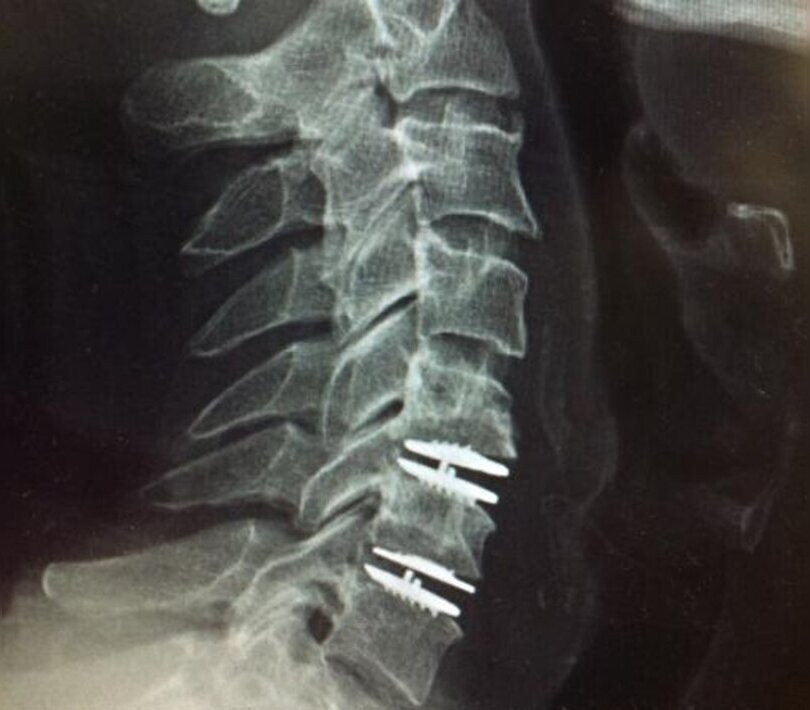

Disc replacement surgery is a cutting-edge procedure to address pain caused by damaged or degenerated spinal discs. By replacing the affected disc with an artificial one, this surgery restores normal spine function and mobility. Ideal for patients with herniated or degenerative discs, it offers a more natural range of motion compared to traditional spinal fusion, providing long-term pain relief and preventing the degeneration of nearby discs.